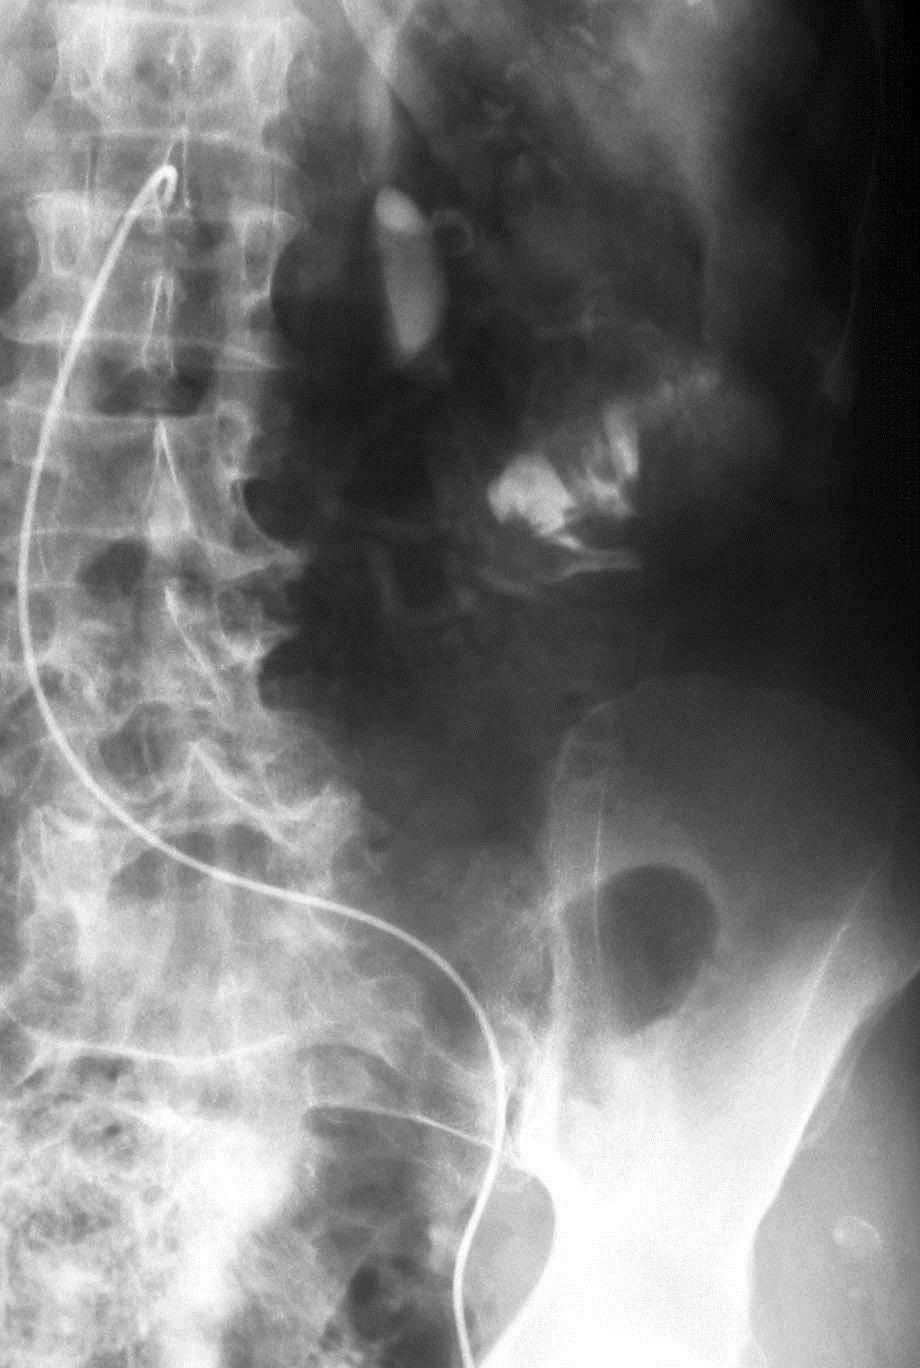

Koval 等人得出结论相似,37例下消化道出血病人,内窥镜和血管造影阴性。动脉灌注肝素5000-10000单位,有或没有血管扩张剂和/或尿激酶。造影剂外溢从32%增加到65%,阴性病例从27%下降到16%[16]。 Malden等人[17]报告10例病人血管造影和内窥镜均为阴性。血管造影前两天已经不再出血,静脉10000单位肝素,500单位尿激酶/小时/3小时。10例病人中仅有2例(20%) 阳性[17],.说明全身用药不如局部用药。 kim 等人[13] 报告,34例病人进行36次激发血管造影。动脉灌注肝素3000-10000,Tolazoline 25-100mg,TPA 10-50mg。造影剂外溢从普通血管造影的0% 增加到31%(11/36)。发现少血管病变从0增加到1.整体诊断有效率为33%。 激发血管造影小结: 1. 激发血管造影尽可能靠近出血发作的时间 2. 与相关临床科室密切合作 3. 血管扩张剂和纤溶药物从怀疑出血部位的动脉灌注 4. 117例激发血管造影病例未见出血并发症 超选择动脉插管术中出血部位的定位 主要技术:使用微导管在血管造影的指导下尽量接近出血病变位置。滞留导管去手术室,外科手术开腹时注射1cc美兰,得到下面的图像 ![]() 优点:确保病变尽量不被丢失;指导病变更为局限性的切除 慢性消化道出血诊断小结 1. 慢性不明原因消化道出血诊断可以是非常困难的 2. 最好的诊断是影像学医生与胃肠内科医生间的合作 3. 介入治疗技术对于慢性消化道出血的角色有限 血管造影遵循Sutton‘s 规则:Go Where the Money Is! ![]() 威利.萨顿(June 30, 1901 – November 2, 1980)